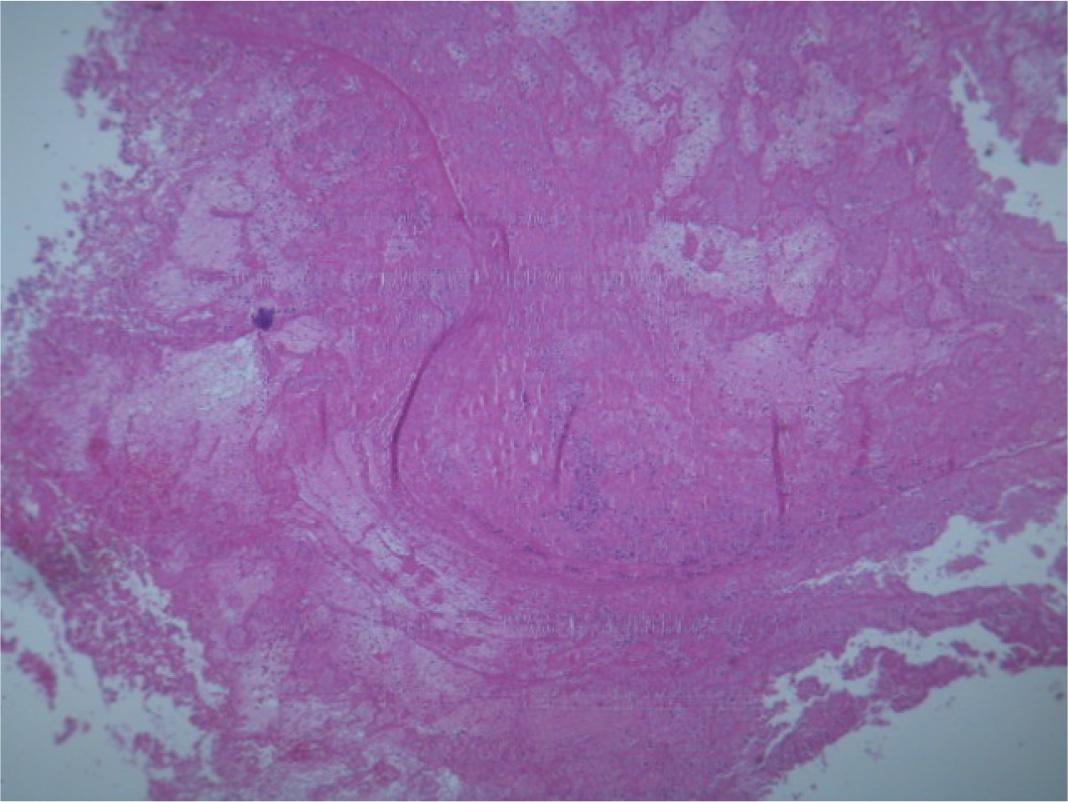

Figure 4

A microscopy image of the clot.